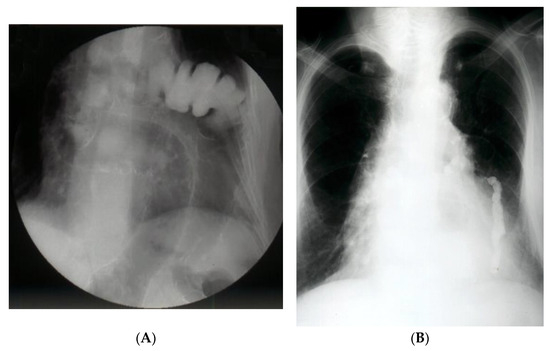

Chest X-ray is most often the first radiological investigation performed in these patients (90%). Chest and abdominal X-ray is recommended to be performed in multiple incidences, including the Trendelenburg position. Specific radiological signs are opacification of the lung bases, especially of the posterior fields depending on the contents of the hernial sac (Figure 1), intrathoracic localization of the abdominal viscera, and left hemidiaphragm elevation (more than 4 cm) with or without atelectasis. In general, diagnosis is more difficult when the hernial orifice is located on the right hemidiaphragm.

The contrasting exam has its advantages in allowing the identification of the digestive viscera by directly opacifying the herniated organ (Figure 2A,B). Furthermore, it can identify upside-down movements, highlighting fixation, incarceration, or even visceral strangulation.

Figure 2. (A). Contrast radiology—irrigography. The intrathoracic presence of the colon is noted through a Bochdalek hernia (A) or post-traumatic (anamnesis) hernia (B).